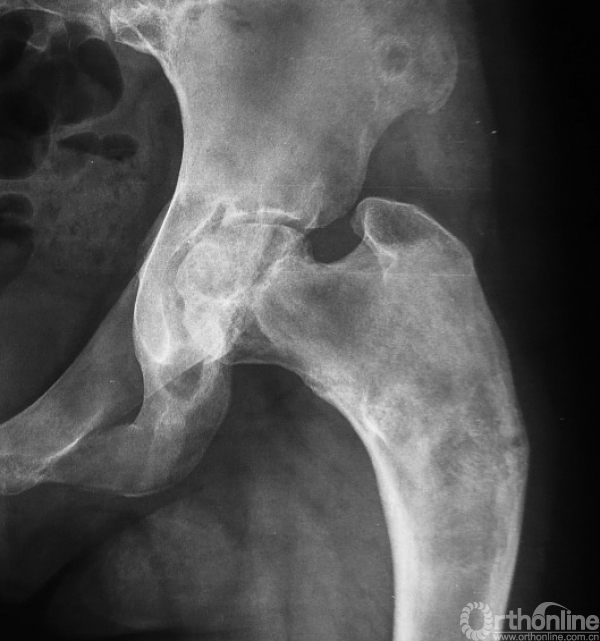

2、囊状改变:在骨纤维异样增殖症中也比较常见(图6),其病理基础为肿瘤内有液化或出血,尤以股骨颈多见,表现为在磨砂玻璃的基础上出现单囊或多囊性膨胀透亮区。

图6 胫骨有明显的囊性变